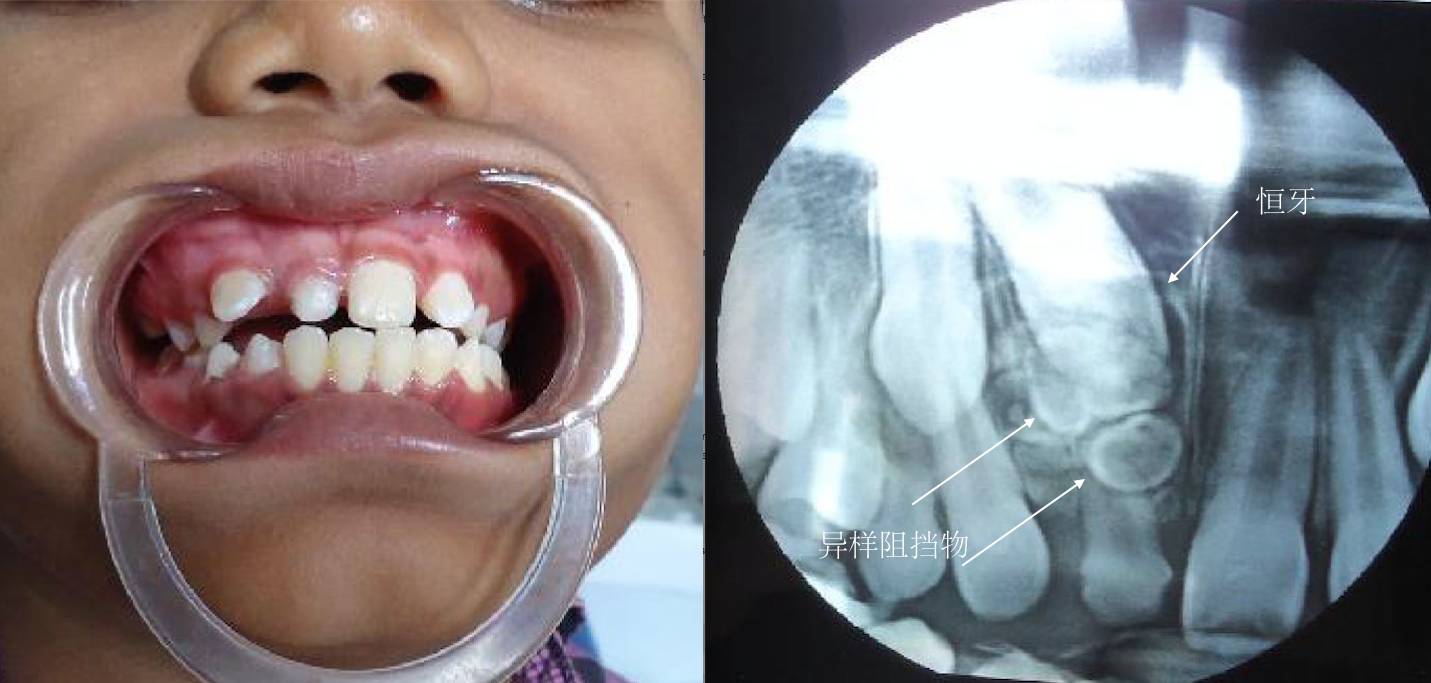

如果牙齿比平均该长牙的年龄,晚了12个月还没有长牙的话,叫做牙齿迟萌。造成牙齿迟萌的原因有很多,比如,多生牙、牙瘤、囊肿会导致牙齿迟萌。

如果你家孩子比平均该长牙的年龄,晚了12个月还不长牙,你需要及时带孩子看牙医了。牙医一般会拍牙片来看看牙床内是否有未萌出的牙齿。

最为常见的是上颌切牙的迟萌。乳切牙因为外伤、蛀牙等原因,造成了过早脱落,致使牙龈反复摩擦增厚,导致下面的恒牙萌出困难,此时需要去进行牙齿助萌。

上颌切牙迟萌